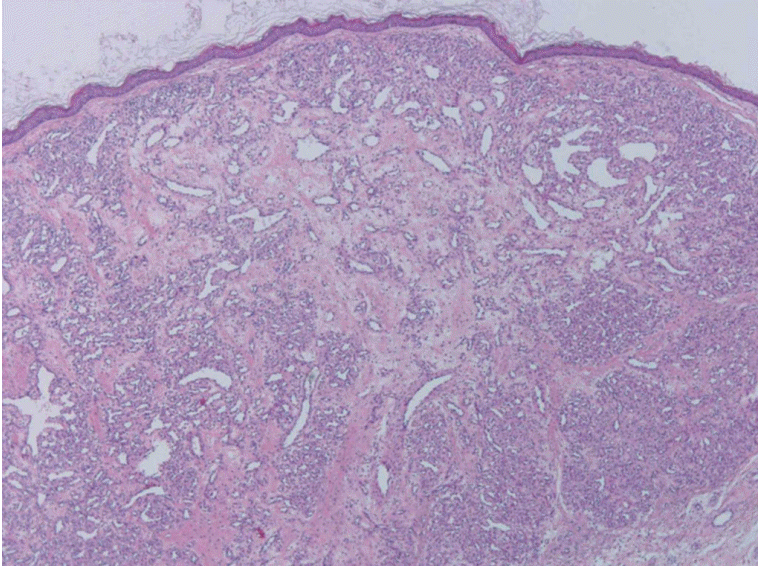

제거한 종물의 크기는 0.8×0.6×0.4 cm 크기로 병리조직학으로 모세혈관들의 소엽성 증식이 관찰되어 모세상혈관종으로 진단되었다(Fig. 4).

Fig. 4.

The photograph of histopathologic finding. Microscopically, the tumor shows lobular proliferation of small capillaries (H&E stain, ×100).